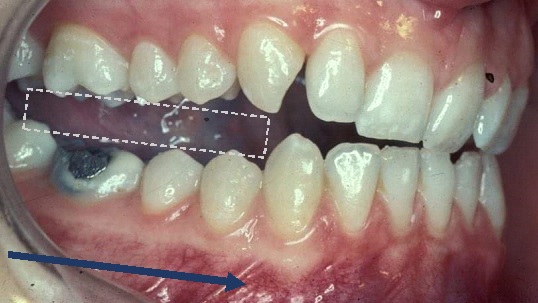

9. 편향 접촉과 간섭

편향 접촉은 하악이 의도한 움직임에서 벗어나도록 하는 접촉이다.[9] 예를 들어 하악이 편향 접촉에 의해 결정되는 경로인 RCP-ICP 슬라이드를 통해 ICP로 편향되는 경우가 있다. 이는 종종 씹기와 같은 기능과 관련이 있지만, 어떤 경우에는 이러한 편향 접촉이 손상을 일으키고 치아 주변에 통증을 유발할 수 있다(종종 이갈이와 관련됨).[19] 그러나 일부 환자는 유사한 편향 접촉을 전혀 인식하지 못할 수 있는데, 이는 접촉 자체보다는 환자의 적응력이 환자의 증상에 영향을 미칠 수 있음을 시사한다.

교합 간섭은 조화로운 하악 운동을 방해하거나 저해하는 모든 치아 접촉(바람직하지 않은 치아 접촉)이다.[9]

비작업측 간섭(사진): 하악이 왼쪽으로 움직일 때(작업측) 조음 용지 또는 플라스틱 심스톡으로 감지할 수 있다. (애버딘 대학교 치과 연구소)

교합 간섭은 다음과 같이 분류될 수 있다:[20]

종류설명

작업측 간섭하악이 움직이는 쪽에 상악 치아와 하악 치아 사이에 과도하거나 조기 치아 접촉이 발생하며, 이 접촉이 전치를 차단할 수도 있고 그렇지 않을 수도 있다.[21]

비작업측 간섭하악이 움직이는 반대쪽에서 발생하는 교합 접촉으로, 하악의 조화로운 움직임을 방해한다. 이러한 간섭은 비스듬하게 향하는 힘 때문에 작업측 간섭보다 더 파괴적일 수 있다.[22]

전방 돌출 간섭상악 후방 치아의 원위 측면과 하악 후방 치아의 근심 측면 사이에 발생하는 접촉. 이러한 간섭은 잠재적으로 매우 손상될 수 있으며, 간섭이 근육에 근접하여 제대로 절단할 수 없게 만들 수도 있다.

치과의사가 수복물을 제공할 때, 이러한 수복물이 간섭을 생성하지 않도록 하는 것이 중요하다. 그렇지 않으면 수복물에 하중이 증가하게 된다. 편향 접촉과 마찬가지로, 간섭도 이갈이와 같은 기능 이상과 관련될 수 있으며(증거는 미약하지만) 과도한 교합력의 분산에 부정적인 영향을 미칠 수 있다. 간섭은 또한 저작근의 활동을 변화시켜 통증을 유발할 수 있지만,[23] 교합과 측두하악 장애 사이의 관계는 논쟁의 여지가 많다.